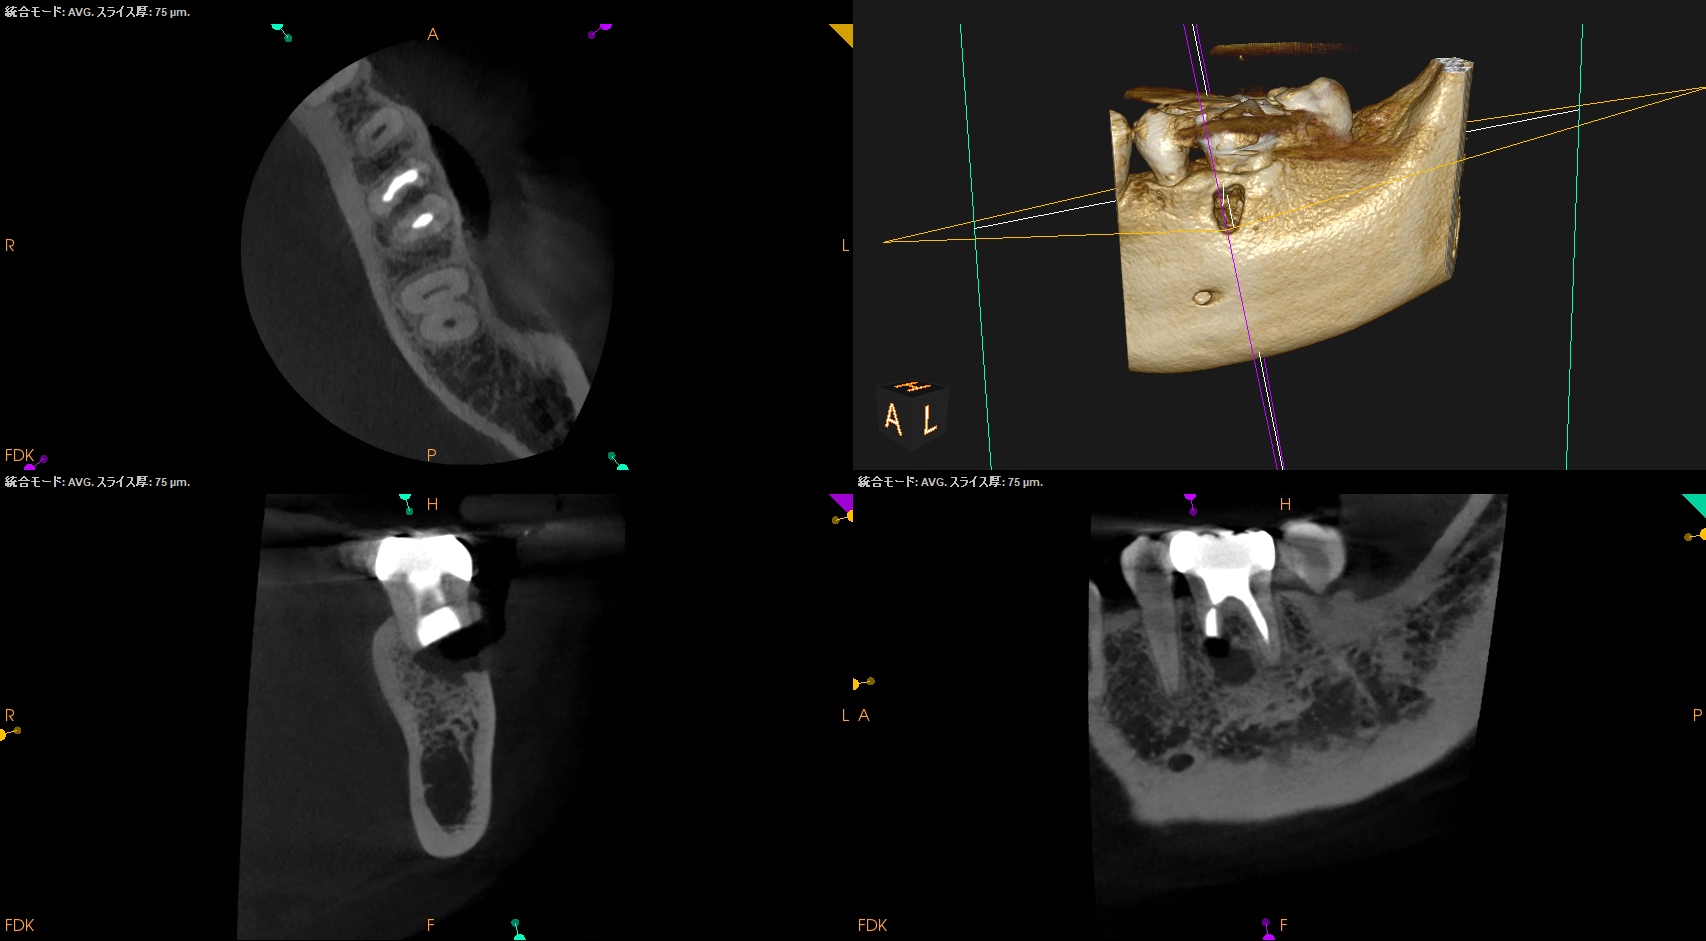

Pre-op Endo(2024.6.17)

#19 Cold N/A, Perc.(+), BT(+), Palp.(-), Perio Probe(WNL), Mobility(WNL)

臨床症状の原因は#19の近心根の根尖病変だろう。

再根管治療に見込みはないため、Apicoectomyなのだが

当該部位を2mm Osteotomyすると#19 MのApexが発見できそこを3mm切断するには頬舌径が6.2mm必要である。